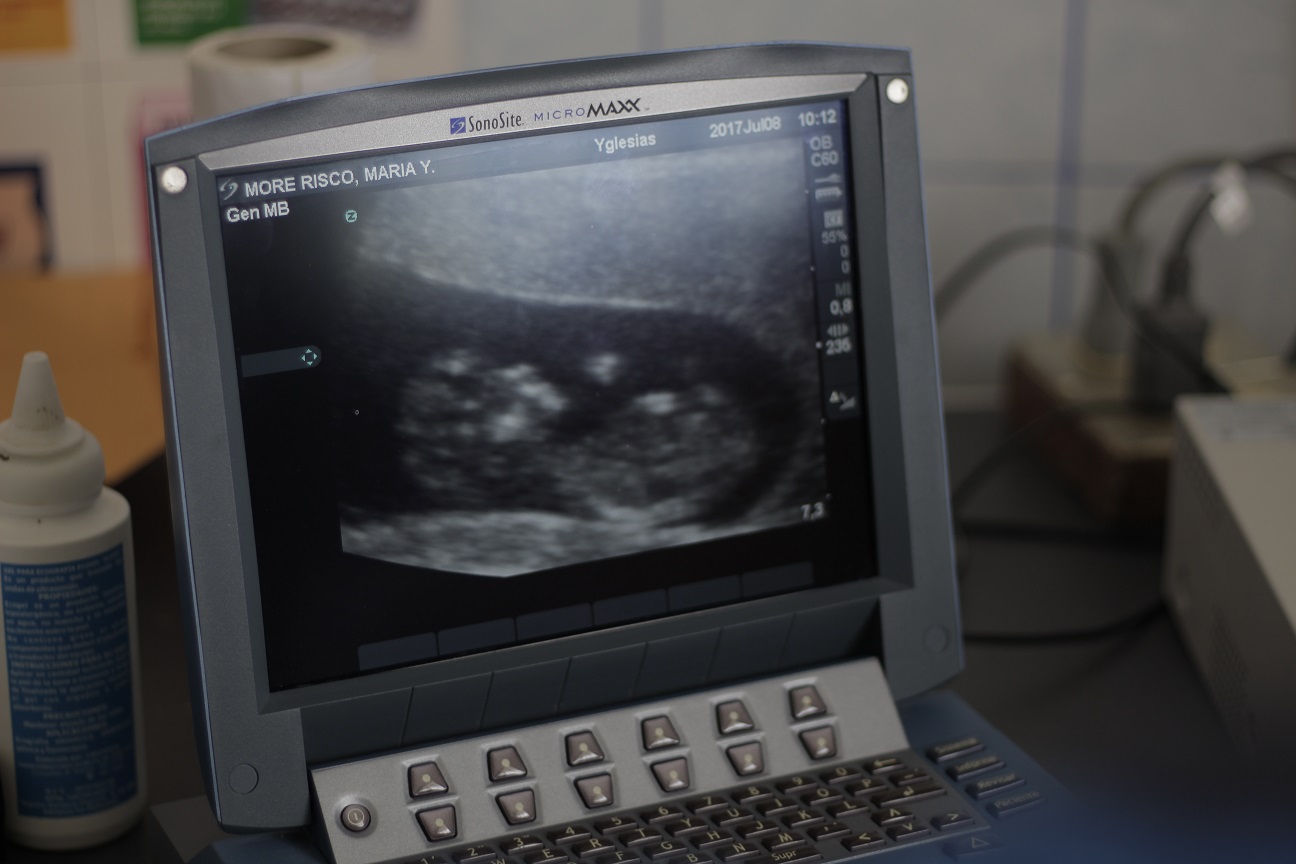

Fueron 30 gestantes quienes gozaron con la atención en odontología, nutrición, psicología, ecografía, evaluación ginecológica y análisis de laboratorio. Cada gestante pudo ver y escuchar a su bebé a través de las ecografías.